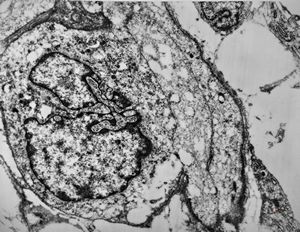

F,69y. | regenerating muscle cell

F,56y. | regenerating muscle cell